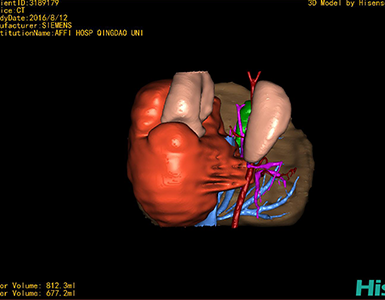

通过调节窗宽窗位调整CT序号,对肿瘤,肝实质,胆囊,下腔静脉,肿瘤,肝动脉、门静脉及肝静脉等进行三维重建;系统自动计算肿瘤体积和肝脏体积。

模拟手术操作,自动计算切除肿瘤体积。肝脏体积为660.9ml,肿瘤体积为812.3ml,肿瘤体积为肝脏体积的122.9%,通过比对3-4岁正常肝脏体积为522.63±121.24 ml,肿瘤所占比例较大,且包裹右侧肾脏、及腹腔大血管,手术无法完整切除肿物,不建议给予手术治疗。